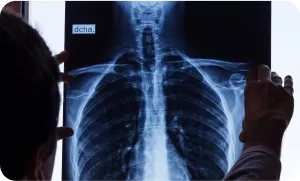

Рентгенография

Рентгенография – малочувствительный метод, поскольку способен распознать деструктивное поражение губчатой кости при размере очага >1 см в диаметре в сочетании с потерей не менее 50% минеральной плотности. Около 20% видимых при остеосцинтиграфии метастатических очагов остаются негативными на рентгенограммах в течение 4–6 месяцев. Значимость традиционной рентгенографии в диагностическом алгоритме костных метастазов снижается. Причина этого, в первую очередь, заключается в достаточно низкой чувствительности метода: продолжительная по времени рентген-негативная фаза не способствует раннему выявлению метастатических поражений костей. Рентгенография может проводиться экстренно и в плановом порядке. Специальной подготовки пациента с подозрением на метастазы в кость не требует.

Преимущество рентгенографии заключается в широкой доступности метода, простоте проведения исследования и возможности быстро получить общую информацию об области последующих исследований, что бывает необходимо при некоторых тяжелых состояниях пациента, в том числе при выраженном болевом синдроме.